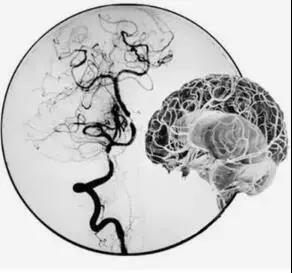

吴主任首先完善脑血管造影(DSA)检查,并详细结合CT、核磁共振检查以及患者右边大脑出现的如虫蛀般大大小小梗塞灶,最终判断疾病“元凶”是罕见的“烟雾病”。

烟雾病是一种进行性血管闭塞,由于患者主干血管闭塞,血液无法供应到大脑,小血管就会拼命扩张,扩张到极限状态,非常容易破裂,造成脑出血,很多患者也是因为出现脑出血才到医院就诊。

“正是因为重要血管无法正常工作,导致患者脑部‘催生’出很多新生异常血管,这些血管很细很密,在血管造影下,就像烟雾一般,因此被称为烟雾病。”吴主任介绍。

DSA脑血管造影发现患者右侧一根主干颈内动脉完全闭塞、对侧的颈内动脉也出现狭窄,这意味着供应脑部血液的四根主要血管,两根都有问题。此时的李女士右边大脑血供差,侧枝循环不理想,左边血管供血少,再发展下去,很可能出现大面积脑梗,如果再不及时采取措施,病情只会越来越重。治疗方法只有一种——“颅内外血管搭桥术”。

通过神经外科医疗和护理团队的精心治疗,患者恢复很快。术后复查脑血管造影颅内吻合口很通畅,MRI检查也提示大脑的侧支循环明显增加、脑血供明显改善。